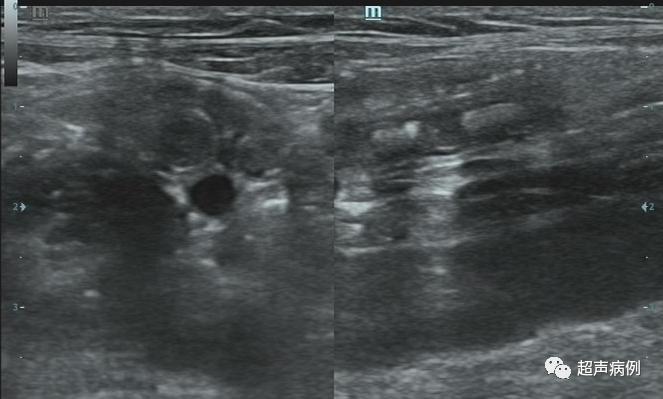

病例3

男,13岁1月。转移性右下腹痛9小时。

超声检查:

在右下腹阑尾解剖区查见一管状低回声,宽约0.77cm,长约4.0cm,其内可见团状强回声伴声影,边界较清,CDFI:边壁可见点状血流信号。

病理诊断:急性化脓性阑尾炎及其周围炎。